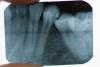

У меня между 5 и 4 зубами снизу был кариес. Еще год назад стоматолог сказала, что нужно сделать его в течении нескольких месяцев, пока, судя по ее снимку он был поверхностный, как она сказала.

Сегодня в ЦНИИС мне сделали снимок, приложенный ниже, и запломбировали два зуба, так как кариес перекинулся на второй. Зуб у меня НЕ болел. Я просто решила его наконец сделать. Более того врач даже сначала сказал, что возможно придется удалять нерв. Однако в процессе он решил просто запломбрировать пораженные области. Он сказал, что если зуб заболит, то придется все же удалять нерв. Это меня не на шутку тревожит, так как в 11 мне уже удалили нервы с передних верхних зубов и теперь с ними куча проблем, очень не хочется умерщвлять зуб.

Подскажите, пожалуйста, судя по снимку какова вероятность, что зуб заболит и нерв воспалится? Какова была область поражения? У меня ничего не болело, когда я пришла сегодня к врачу!

По снимку не скажешь воспален нерв или нет! Для этого нужно ЭОД! Не известно что врач использовал в качестве прокладки!До тех пор пока зуб не болит и нет в нем дискомфорта можете смело гулять! Но как только он заболит тут хочешь не хочешь. но нерв придеться удалять!!!